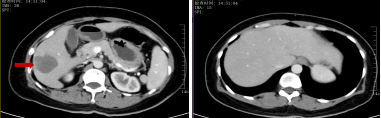

治疗前:肝脏多发转移瘤

治疗后:肝右叶转移瘤显著缩小,

其余小转移瘤消失

2024-12-26 开始患者进行「贝伐珠单抗 500 mg d1+奥沙利铂 200 mg d1+卡培他滨 1 g 1/早餐后 1.5 g 1/晚餐后 d1-14 Q3w」方案治疗,在 2 周期治疗后患者黑便消失,腹痛、腹泻缓解,贫血改善,血红蛋白升至 91 g/L,体力状况恢复(ECOG:0 分),生活质量明显提升,复查上腹部+盆腔 CT:结肠肝曲病变稳定,肝脏异常强化影较前明显缩小,最大约 7.3 cm×6 cm,初步治疗后疗效显著。继续 6 个周期的系统治疗后,全面复查结果带来了振奋人心的消息:肿瘤标志物大幅下降,CEA(正常值<5ng/ml)从初始的 23.2ng/mL 降至 2.3ng/mL,CA199(正常值<30U/ml)从 479U/mL 降至 25U/mL,肝脏小的转移灶消失,最大的转移灶从 11 cm 显著缩小至 6 cm,原本广泛的肝转移灶得到了有效控制,这意味着转化治疗取得了成功,原本无法手术的晚期病灶,终于退缩到了可以手术切除的范围。